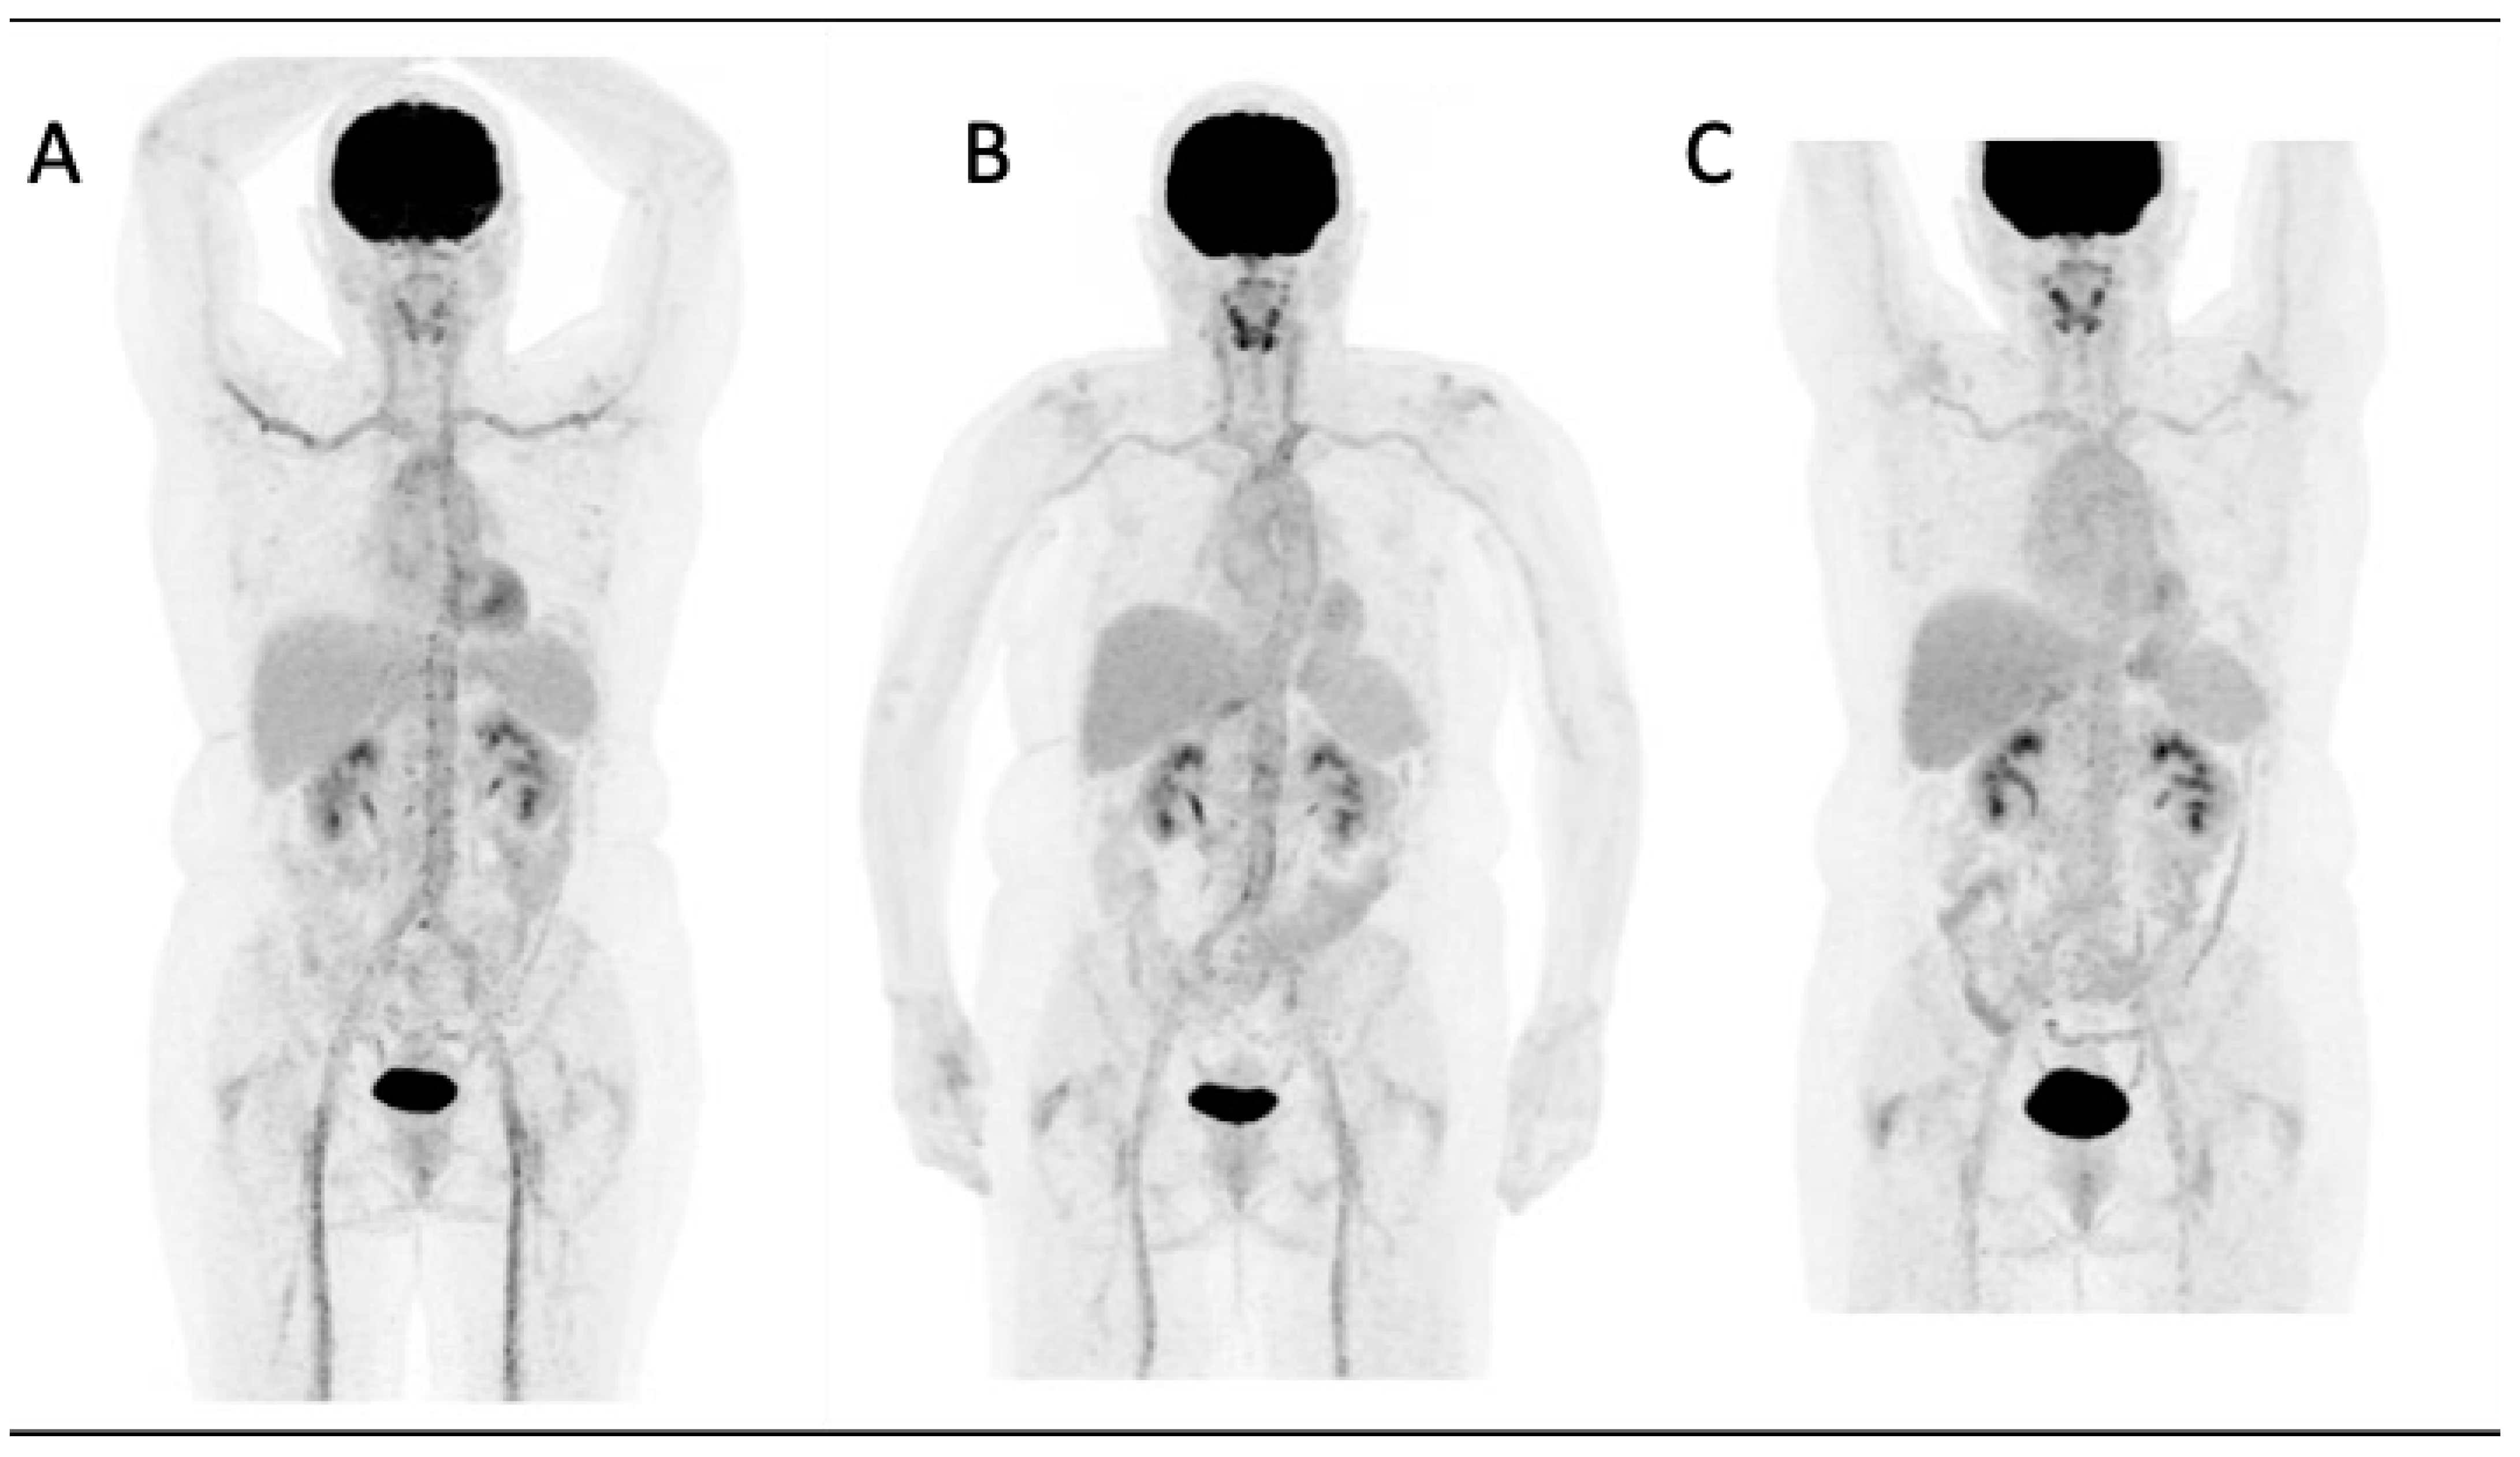

Figure 1 illustrates a case of GCA at the time of diagnosis and its subsequent post-therapy follow-up.

Figure 1.

A 66-year-old woman diagnosed with giant cell arteritis. (A) FDG-PET whole-body MIP image shows increased FDG uptake in the aorta, carotid, subclavian and iliac arteries. FDG uptake is higher than liver uptake (grade 3 according to the Meller scale) and thus categorized as pathologic. After treatment with tocilizumab and steroids a progressive improvement was observed transitioning from grade 2 (B) to grade 1 (C).